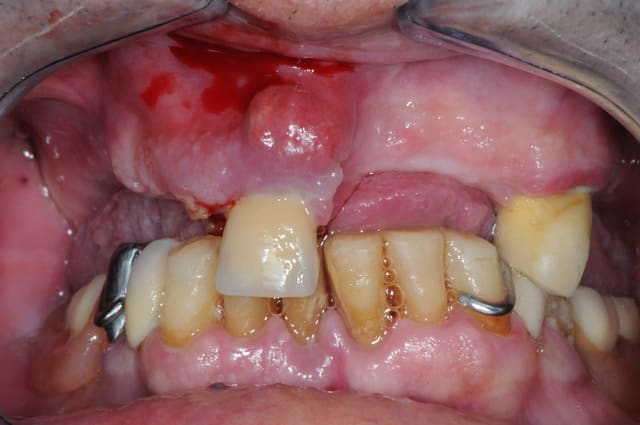

Ca y est, j'en tiens un !

Désolé pour la photo, l'appareil était là par hasard mais sans son flash.

Ce patient n'a pas vu de dentiste (ni de brosse à dent) depuis 40 ans. Le motif de consultation est une "légère gêne" à la mastication côté gauche.

Admirez le mouvement poétique et gracieux de la 47, figé en plein élan telle une danseuse.